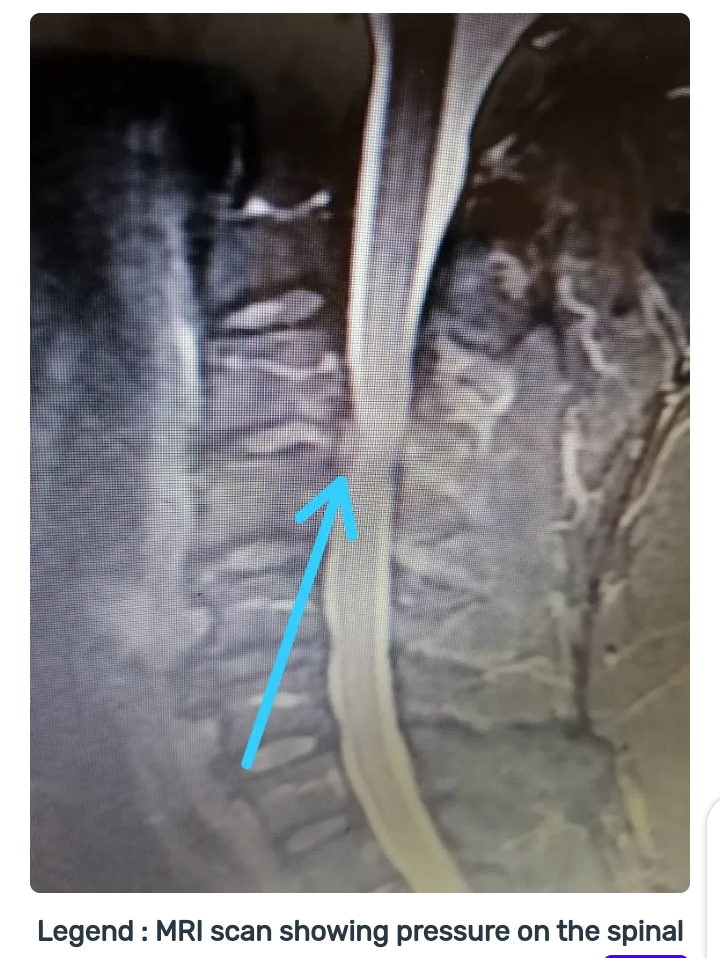

We did tests and found that he had arthritis in the neck. This is called cervical spondylosis. He had pressure on his spinal cord (Cervical spondylotic myelopathy (CSM) and we advised that he should have surgery. He said ‘okay’. And we never saw him again!